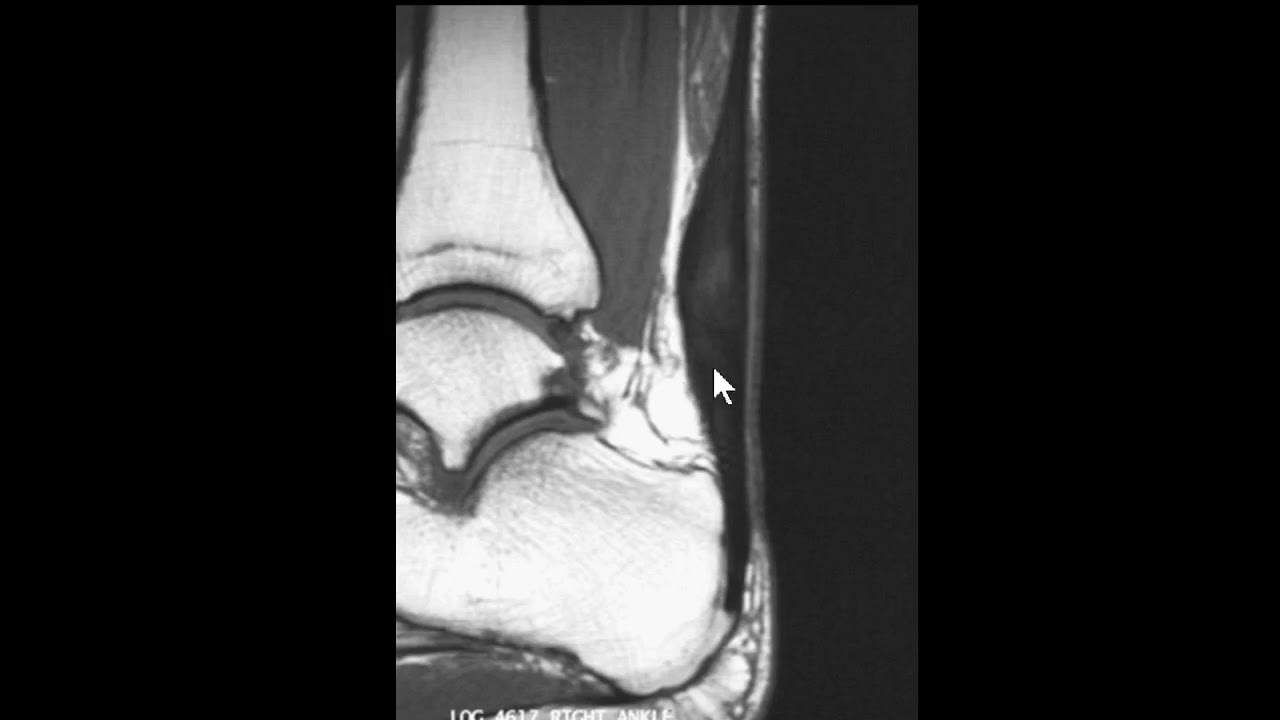

saudações vamos aqui a Mais Um Caso o contexto clínico é de um paciente que sofreu uma torção aguda do tornozelo e temos essa ressonância magnética aqui um axial DP com saturação de gordura e vamos observar aqui aqui é a fíbula corte aqui no plano axial aqui a fíbula aqui o talos aqui a tíbia né então o ligamento tíbio talar anter inferior está íntegro vamos descendo aqui aqui é a topografia do ligamento talofibular anterior aqui o ligamento talofibular posterior e você observa aqui no ligamento talo fibular anterior veja que ele está espessado está com hipersinal e

você nota nitidamente uma solução de continuidade né uma ruptura aí do ligamento talofibular anterior e edema ao seu redor existem outras alterações mas a gente vai se ater a essa alteração o ligamento talofibular posterior ele tem esse aspecto radiado né rajado é normal e o ligamento calcâneo fibular esse aqui na ponta da seta está íntegro apesar de haver edema ao redor dele então o ligamento talo fibular anterior rompeu e essa é a rotura mais frequente ligamentar no tornozelo do ligamento talofibular anterior aqui pra gente ver um comparativo com um tornozelo normal você Observe aqui a

fíbula aqui o talos e aqui você vê o ligamento talo fibular anterior aqui é uma sequência T1 e aqui uma sequência T2 com saturação de gordura você veja aí o ligamento talofibular anterior veja como ele é né em condições normais aí o ligamento talofibular anterior aqui o talo fibular posterior n talo fibular posterior ele tem esse aspecto rajado e descendo um pouco mais o calcâneo fibular fininho aqui subindo calcando fibular saio daqui e vem para cá mas o importante aqui É vermos o ligamento talo fibular anterior normal o aspecto normal dele ok Neste vídeo era